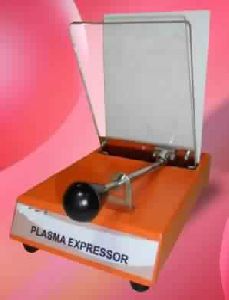

Plasma Extractor / Expressor

Plasma Extractor is designed to Extract Blood component from centrifuged Blood Bags. The spring loaded front panel applies pressure on the collected bag causing the liquid to contain in transfer bag. Its sturdy construction makes it durable and reliable, easy to use and portable. The unit is available in both versions automatic and manual.